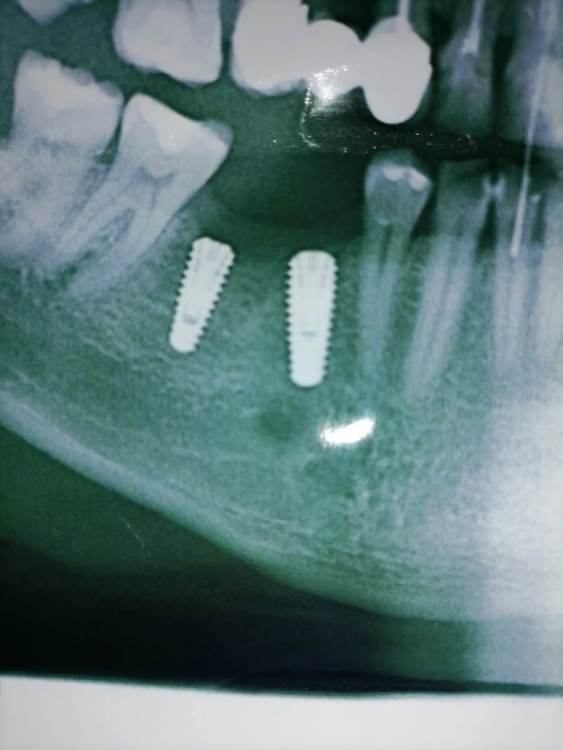

На снимке оголилось 2 витка резьбы

Добрый день уважаемые доктора. После установки коронок на импланты, беспокоит что на контрольном снимке оголилось 2 витка резьбы импланта.

Сами импланты установлены в ноябре.  Коронки на них поставили месяц  назад, закрутили с усилием 25 ньютонов, и поставили временную пломбу . Отправили на месяц гулять. Сегодня сделал снимок, пришёл к врачу врач сказала что все отлично. Докрутила на 35 и поставила постоянную пломбу. Но меня беспокоит что ушло несколько витков резьбы, хотелось бы услышать ваше мнение, скажите это нормально? По ощущениям ничего не беспокоит, жую без проблем.